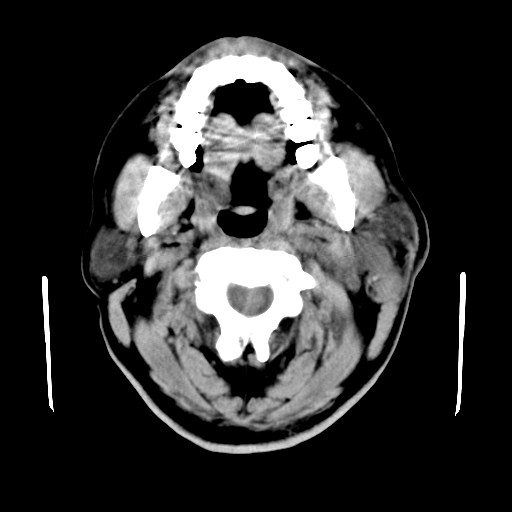

以下是引用卜一在2007-8-6 21:23:00的发言:[br]定位:左侧胸锁乳突肌内侧 颌下腺下后方。特征:弥漫性生长 软组织密度肿块,界限不清,内隐约见低密度坏死。考虑:神经源性肿瘤或血管源性肿瘤。

以下是引用wangzhanshuang在2007-8-6 21:08:00的发言:[br]腮腺混合瘤